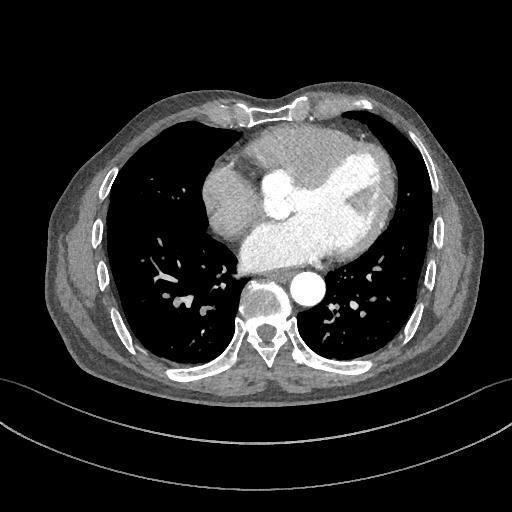

下图的胸部CT平扫,有什么致命的问题?

图7

仔细一看,主动脉里面有线样阴影!并且,线样阴影两边的密度一高一低!

图8